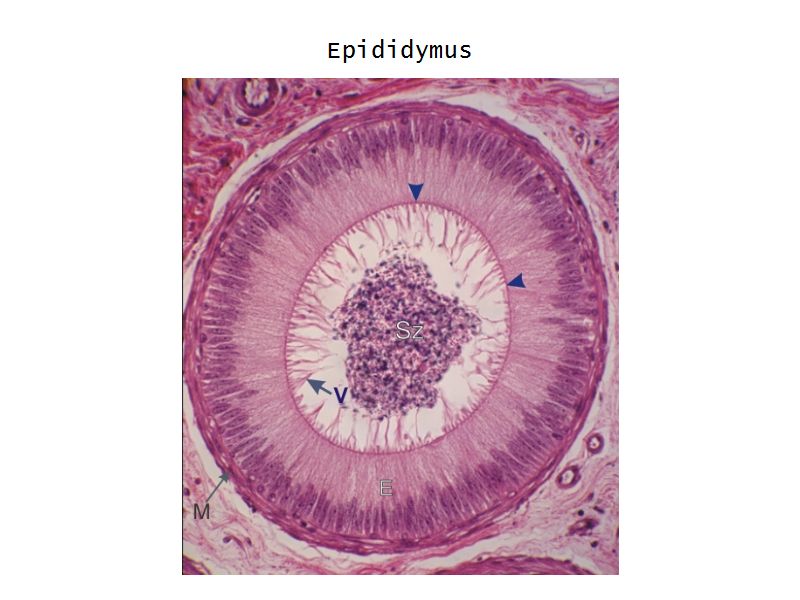

Epididymus

- Long convoluted duct

- With fibrous covering

- Inside visceral layer of tunica vaginalis testis

Epididymus

- Simple ciliated columnar epithelium

- Tall ciliated cells

- Elongated nuclei away from BM

- Low absorptive cells

- Spherical nuclei close to BM

- Surrounded circular smooth muscle